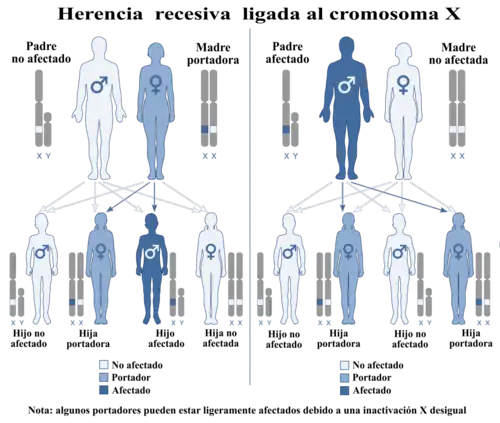

Herencia

El daltonismo es hereditario y se transmite por un alelo recesivo ligado al cromosoma X. Si un varón hereda un cromosoma X con el alelo alterado será daltónico. En cambio en el caso de las mujeres, que poseen dos cromosomas X, solo serán daltónicas si sus dos cromosomas X tienen el alelo alterado. Por ello el daltonismo afecta aproximadamente al 8 % de los hombres y solo al 0,5 % de las mujeres.[7]

El daltonismo es de origen genético, hereditario y presente desde el nacimiento. Los mecanismos que lo provocan están relacionados con la funcionalidad de los conos situados en la retina y con la expresión de las opsinas, los fotopigmentos que convierten la luz en señales químicas. Esta causado por mutaciones de los genes que codifican las proteínas opsinas. La forma más común de daltonismo es el daltonismo rojo-verde congénito, que incluye la protanopía/protanomalía y la deuteranopía/deuteranomalía. Estas afecciones están mediadas por los genes OPN1LW y OPN1MW situados en el cromosoma X, dado que estos genes son recesivos afectan con mucha más frecuencia a hombres que a mujeres. El daltonismo azul-amarillo es menos frecuente, está provocado por mutaciones en el gen OPN1SW ubicado en el cromosoma 7.